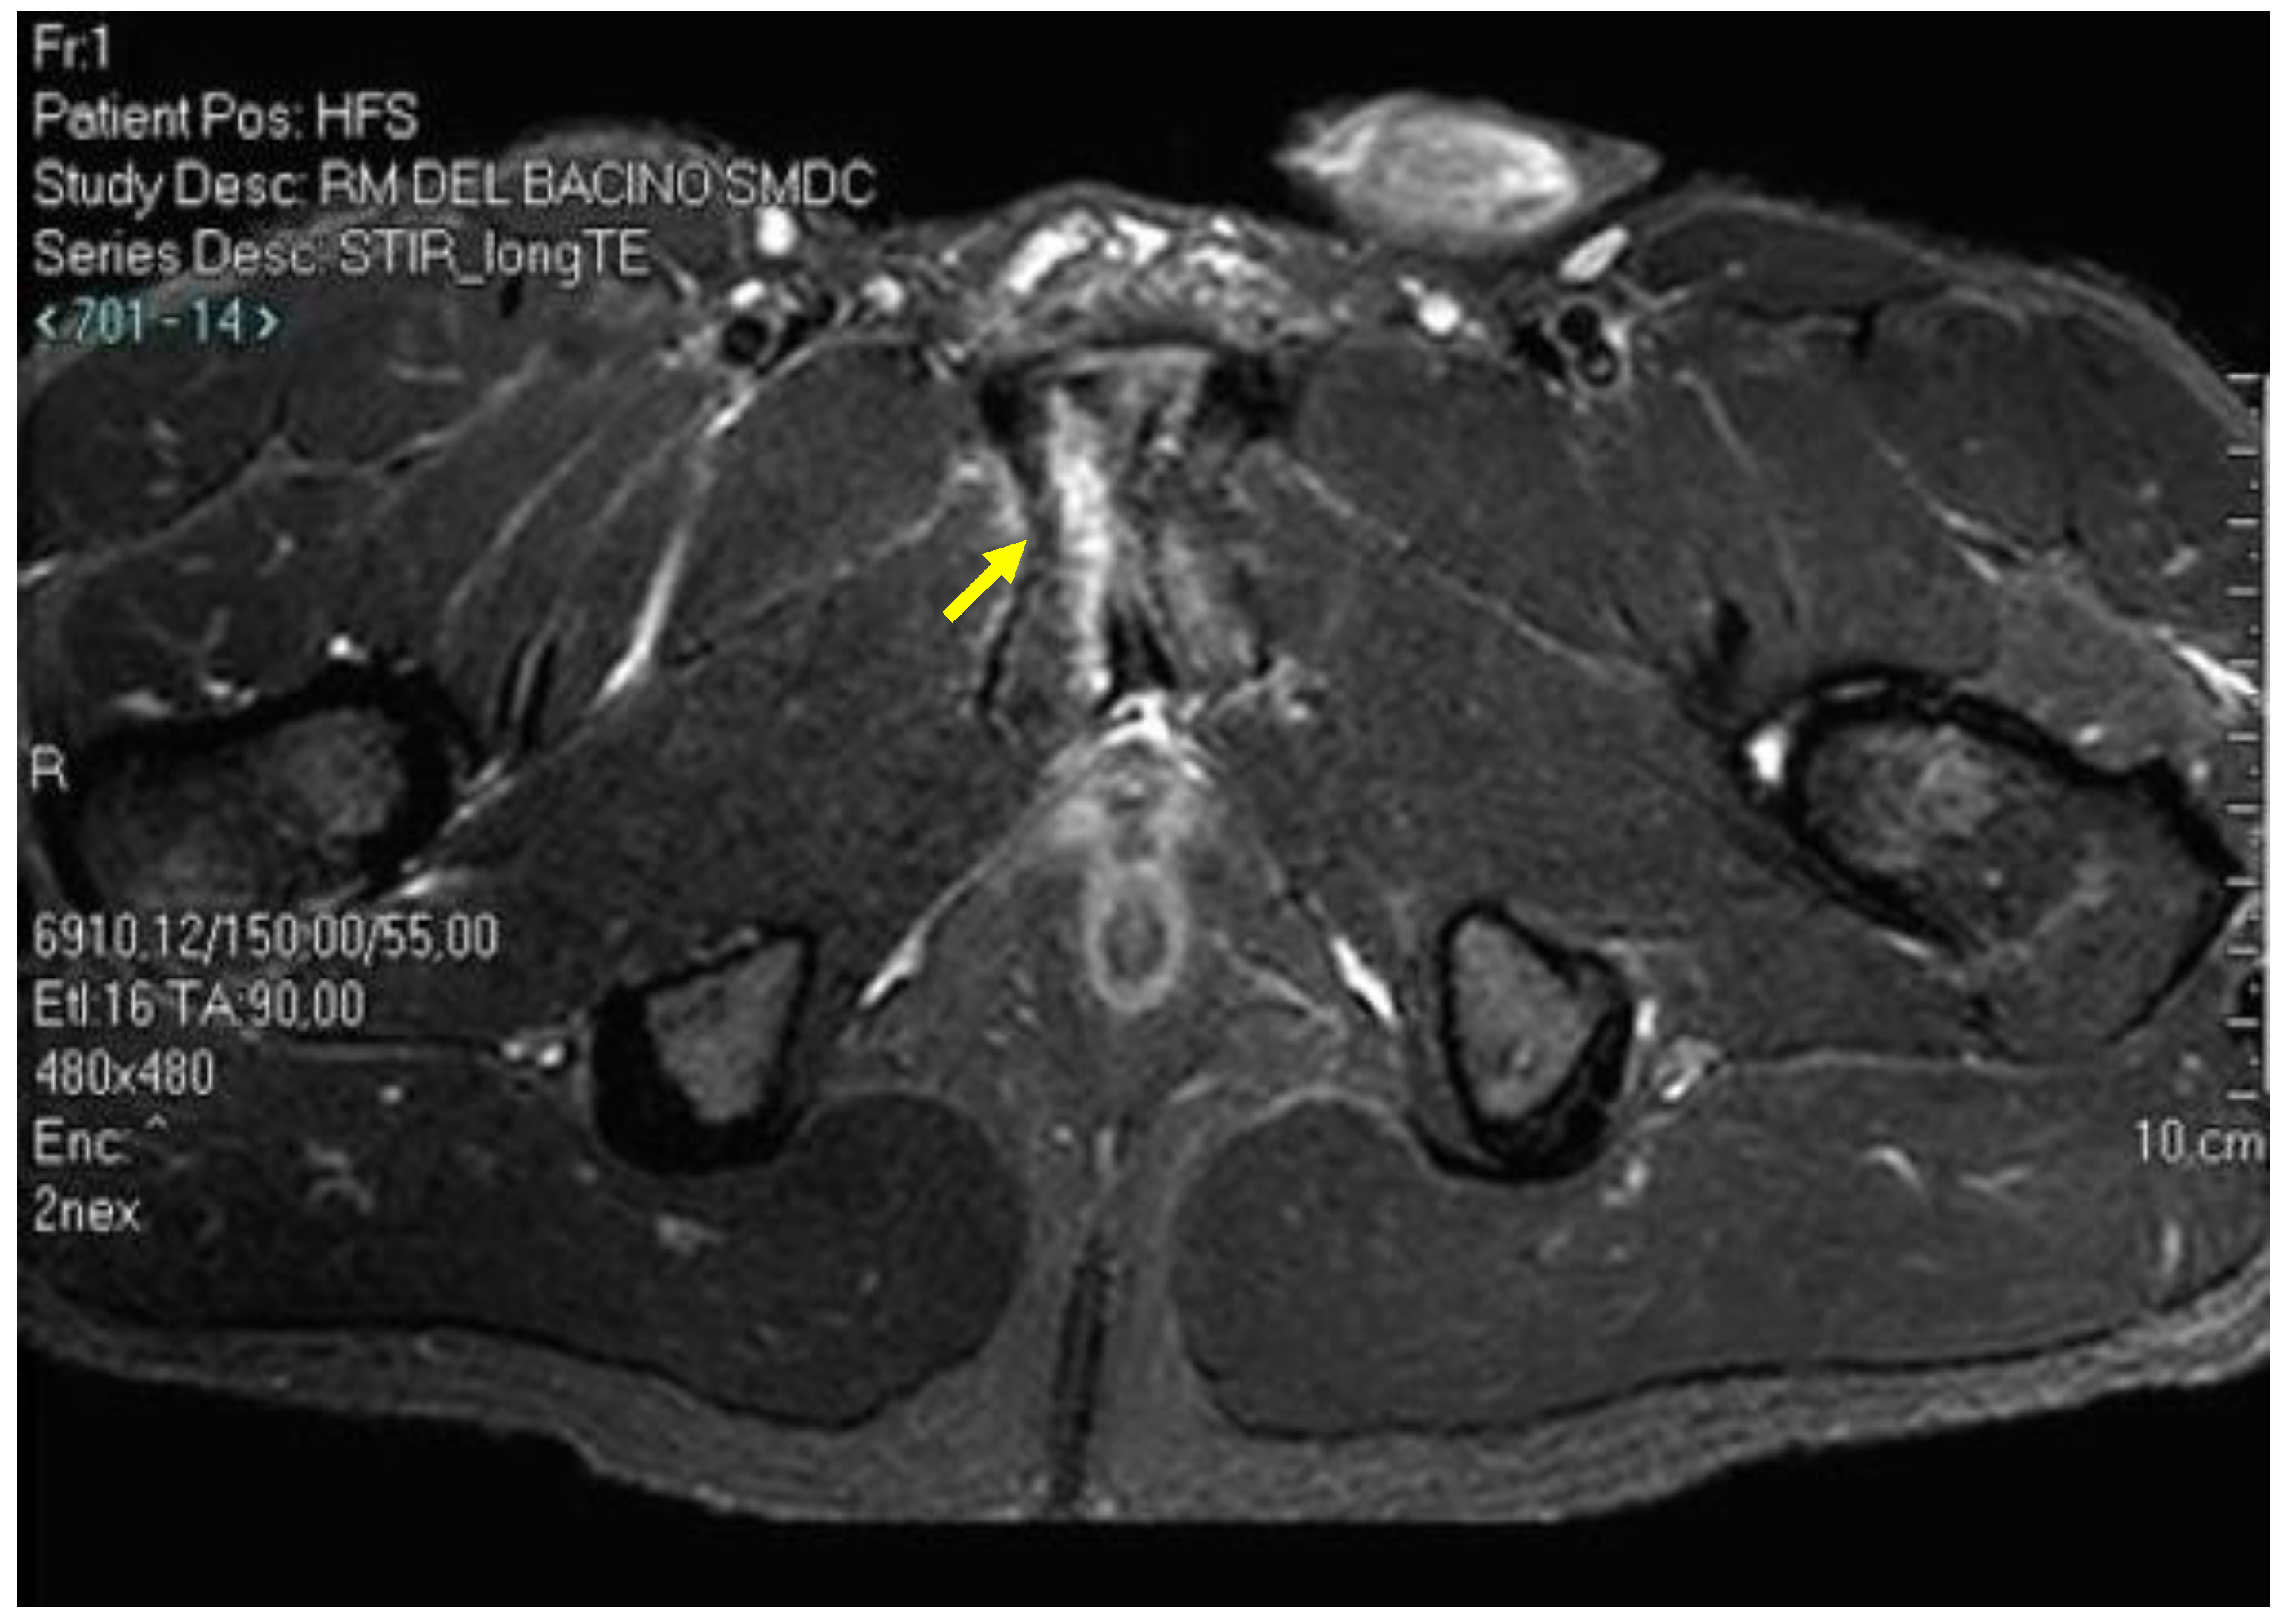

| Bone marrow oedema | Coronal T1; coronal T2 FS; axial oblique T2 FS; axial oblique PD FS | Signal hyperintensity in the fluid-sensitive sequences. Signal hypointensity in T1 sequences. Grade 1: BMO ≤ 1 cm; Grade 2: BMO ≥ 1 cm and ≤2 cm; Grade 3: BMO ≥ 2 cm. |